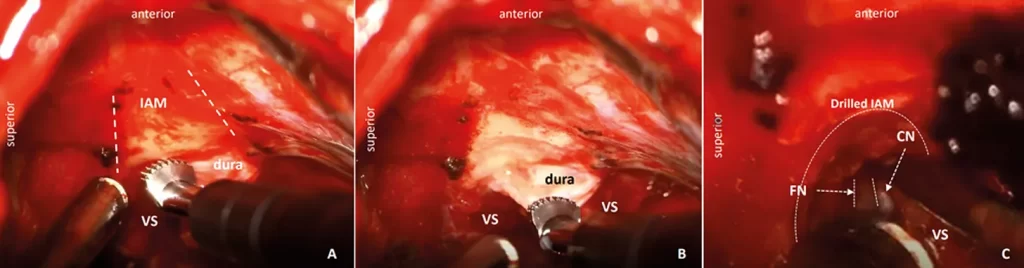

Figura 1:

A) Imágenes intraoperatorias de una resección de schwannoma vestibular (SV) derecho, mostrando la punta del aspirador ultrasónico de hueso con las micro garras, con el área del conducto auditivo interno (CAI) marcada con líneas discontinuas;B) El hueso del CAI se elimina de forma progresiva, mientras que la duramadre permanece intacta;C) La exposición permite identificar el nervio facial (NF – líneas punteadas) en el CAI, y también se identifica el nervio coclear (NC). La línea curva muestra el área del hueso del CAI que ha sido removido.